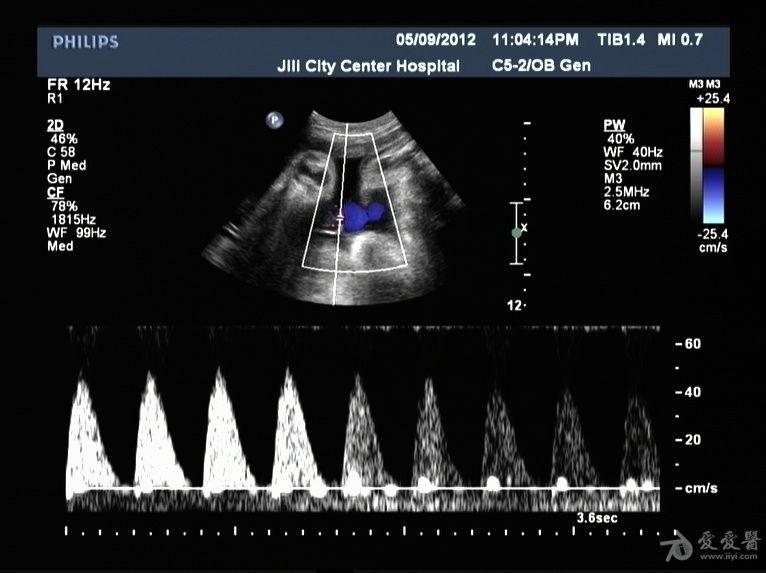

胎儿脐动脉血流频谱呈单峰有什么特别的意义吗

脐动脉舒张期血流消失或反向